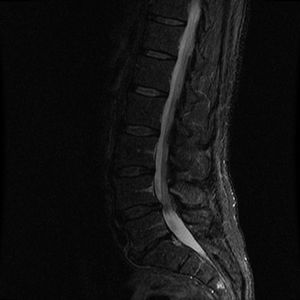

7. 1. 영상의학적 진단

허리뼈 질환은 X선, CT, MRI 등 영상의학적 검사를 통해 진단할 수 있다. MRI는 척추, 추간판, 신경 등 연부 조직의 상태를 자세히 확인할 수 있어 척추 질환 진단에 유용하게 사용된다.